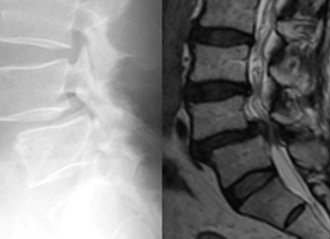

第4腰椎に前屈時に増強するすべりを認め不安定性を示しています。

MIS-TLIF(低侵襲腰椎後方椎体間固定術) 椎間板にケージと言われるスペーサーが挿入され、また経皮的に椎弓根スクリューの挿入とロッドの連結がなされ、第4腰椎のすべりが矯正され固定されています。